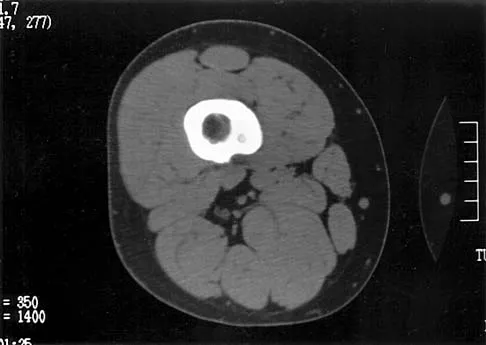

Question 49High Yield

A 46-year-old man has incomplete paraplegia after being involved in a motor vehicle accident. The CT scan shown in Figure 5 reveals marked canal compromise. What is the most appropriate management to improve neurologic status?

Explanation

According to a study by the Scoliosis Research Society, the use of anterior decompression is most predictable for improving neurologic status. This is particularly true of bowel and bladder functional loss. Laminectomy is contraindicated because it further destabilizes the spine. Posterior instrumentation and indirect reduction through distraction and ligamentotaxis only incompletely decompress the compromised canal and are successful only if performed within 48 hours of injury. While some improvement may occur with closed management, the amount of recovery is less than that achieved with surgical decompression. A posterior approach and instrumentation may be added to the anterior decompression based on the characteristics of associated injuries to the posterior element. Gertzbein SD: Scoliosis Research Society multicenter spine fracture study. Spine 1992;17:528-540. Garfin SR, Vaccaro AR (eds): Orthopaedic Knowledge Update: Spine. Rosemont, IL, American Academy of Orthopaedic Surgeons, 1997, pp 197-215.